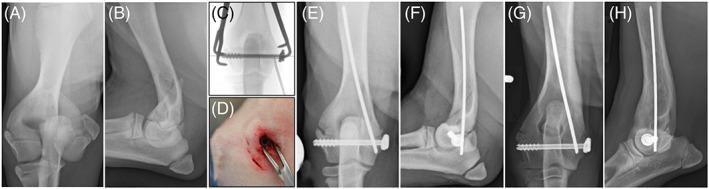

To summarize and discuss peer-reviewed studies on minimally invasive osteosynthesis (MIO) of long bone, physeal, and articular fractures in dogs and cats.

More than 40 MIO articles have been published in the last 15 years, but most studies had small numbers, lacked control groups, and used limited outcome measures. Studies generally showed that MIO was feasible in dogs and cats with low complication rates. The current evidence does not demonstrate superior bone healing or functional outcomes with MIO when compared to standard methods. Although treatment principles, case selection, and techniques varied depending on the anatomical location, there were no salient differences in complication rates among long bones, physeal, and articular fractures treated by MIO.

The current available evidence and the personal experience of the authors support MIO as a promising fracture management modality. MIO can yield excellent outcomes when applied in carefully selected cases, performed by surgeons experienced in the technique. We cannot, however, conclude that MIO is superior to open fracture stabilization based on the available evidence in veterinary literature. Randomized controlled studies are warranted to prospectively compare MIO with other osteosynthesis techniques and thereby validate its role in fracture management for dogs and cats.